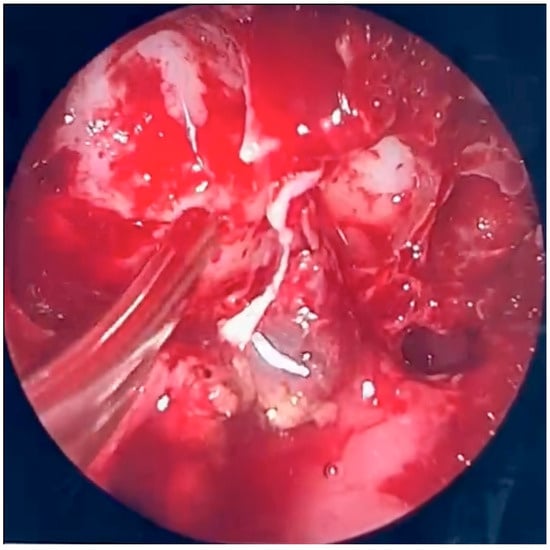

Initial, pre-operative CT scans with massive inflammatory opacifications are presented in Figure 2.

During further inspection, a bony defect of the lamina papyracea was identified in its anterior portion, measuring approximately 4 mm in diameter. The lamina papyracea was resected further, extending posteriorly to the level of the posterior ethmoid cells. A horizontal incision was then made in the orbital periosteum, which allowed for partial herniation of the orbital fat into the ethmoid cavity—facilitating access and drainage. Anterior nasal packing using Merocel was placed to support mucosal healing and maintain patency. Figure 3, Figure 4 and Figure 5 present the intraoperative view.

Figure 3. Endoscopic surgery: intraoperative view showing nasal cavity filled with fungal masses.

Figure 4. Endoscopic surgery: intraoperative view after removal of fungal infiltration to the level of the skull base. Opening of the sphenoidal sinus seen inferiorly (6 o’clock position). The upper-left part of the picture (11 o’clock position) shows the site of orbital periosteum incision with partial herniation of orbital fat into the ethmoid cavity. Two images obtained from the same projection.

Figure 5. Endoscopic surgery: intraoperative view of the right maxillary sinus after removal of fungal masses. Opening of the sphenoidal sinus visible on the right (4 o’clock position).